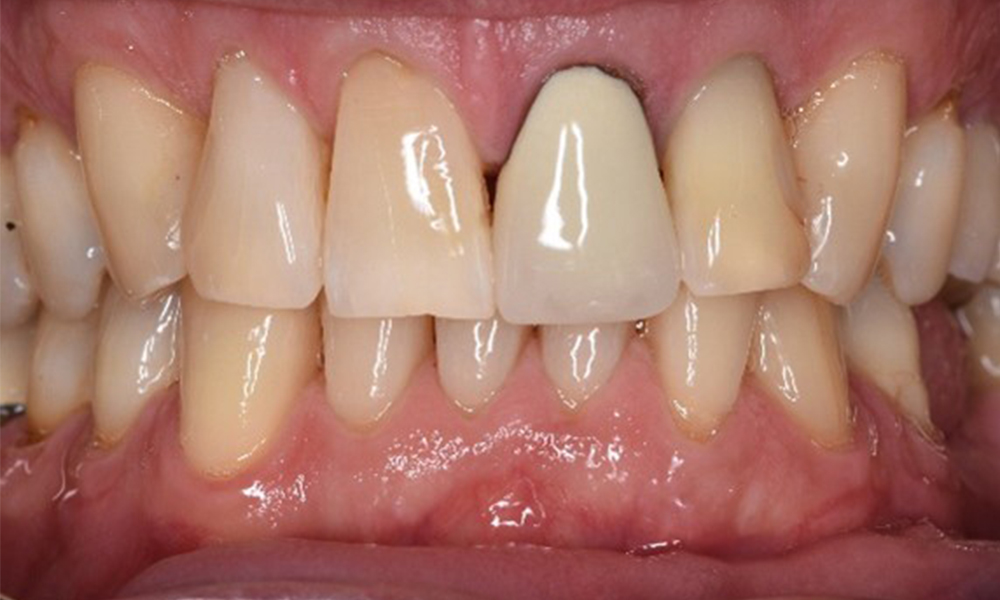

In the medical history, the 55-year-old patient states that he has no systemic disease and is not taking any medication. The patient’s lifestyle is similarly unremarkable. The patient has a few tooth restorations and two implants (2nd and 4th quadrants). On the basis of current findings, gingivitis is identified in an otherwise stable periodontal condition on the reduced periodontium (stage III, grade A).

Previous treatments: dental restorations (non-precious metal/ceramic blend), two implants (2nd, 4th quadrants)

Despite the stable condition, it is also important for this patient to be given motivation/instruction. Particular attention should be paid to correct care for implants. Here in particular, good at-home maintenance can have a significant impact on the long-term stability of oral and implant health.